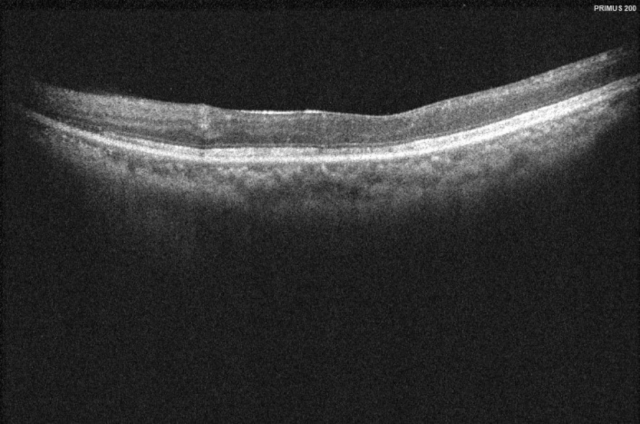

依托“港澳药械通”政策优势,广州市第一人民医院南沙医院(下称“广州市一南沙医院”)于2023年底成功引进治疗眼底病的进口药物“布西珠单抗”,成为广州首家引进该药物的公立医院。近期,多名眼底病患者在该医院完成注射治疗,从而改善了视力,实现长效疾病控制。唐先生治疗前影像检查3年前,52岁的唐先生(化名)右眼视力下降明显,同时伴有眼前黑影,视物变形。经过医院检查,被确诊患有糖尿病视网膜病变。此前,他已经进行了多次第一代抗VEGF(...